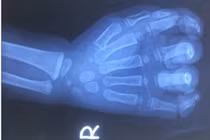

| Người trưởng thành khỏe mạnh không cần bổ sung canxi và vitamin D. (Ảnh minh họa: Brightside) |